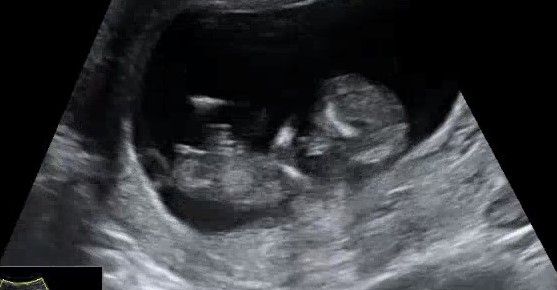

Девчушка 🎀

Если не секрет узнали кто у Вас? У меня узи очень похоже с Вашим.думаю девочка